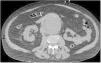

Paciente varón de 71 años, con antecedentes de hipertensión arterial y monorreno (riñón único derecho). Acude a consulta por dolor súbito en fosa iliaca derecha irradiado a ingle ipsilateral. A la exploración se encuentran masa pulsátil infraumbilical y soplo continuo en mesogastrio. Ingresa en Unidad de Cuidados Intensivos (UCI) obnubilado con marcada inestabilidad hemodinámica y taquicárdico. En la tomografía computarizada (TC) de abdomen basal se observa un gran aneurisma de aorta abdominal infrarrenal con signos de sangrado perianeurismático (flecha en fig. 1). Tras la administración de contraste se objetiva comunicación entre la pared posterolateral derecha del aneurisma y la vena cava inferior, compatible con una fístula aortocava (flecha en corte axial fig. 2A y coronal 2B). Los hallazgos se confirman en la reconstrucción tridimensional realizada (fig. 3). Se decidió colocación de endoprótesis por parte de cirugía cardiovascular. Finalmente, el paciente presentó episodio de colitis isquémica y choque séptico, siendo exitus a los siete días.